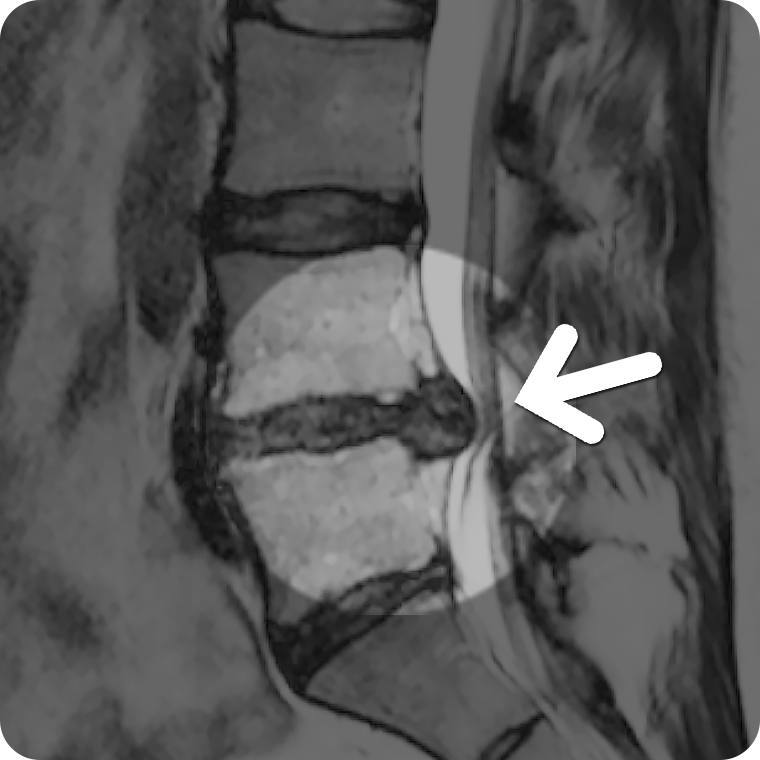

• ˻ ڷ(MRI, CT,X-ray), ˻(ǵ)